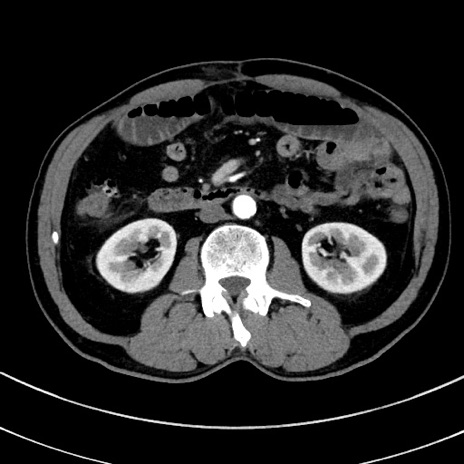

症例8(横断像)

【症例】 60歳代男性

【主訴】 黒色吐物

【現病歴】 4日前から嘔気自覚、2日前の朝食後にも嘔気あり、自分で手で嘔吐反射起こし嘔吐したところ血が混ざっていたため受診。

【既往歴】 5年前汎発性腹膜炎を伴う急性虫垂炎で手術、高血圧、前立腺肥大症、高脂血症

【身体所見】 腹部正中に手術癩痕あり 腹部平坦・軟圧痛なし膨満感あり

【データ】WBC 8400、CRP 4.54